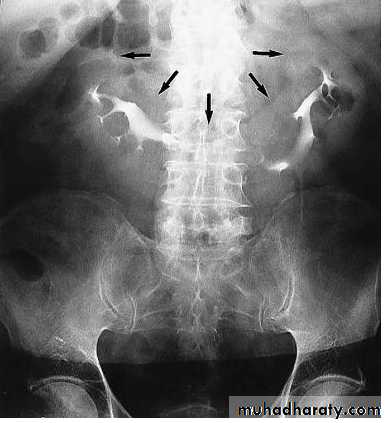

Infestation With Schistosoma haematobium. Plain radiograph demonstrates calcification in the wall of the bladder (open arrows) and in the wall of the left ureter (curved arrow). The bladder is filled with urine